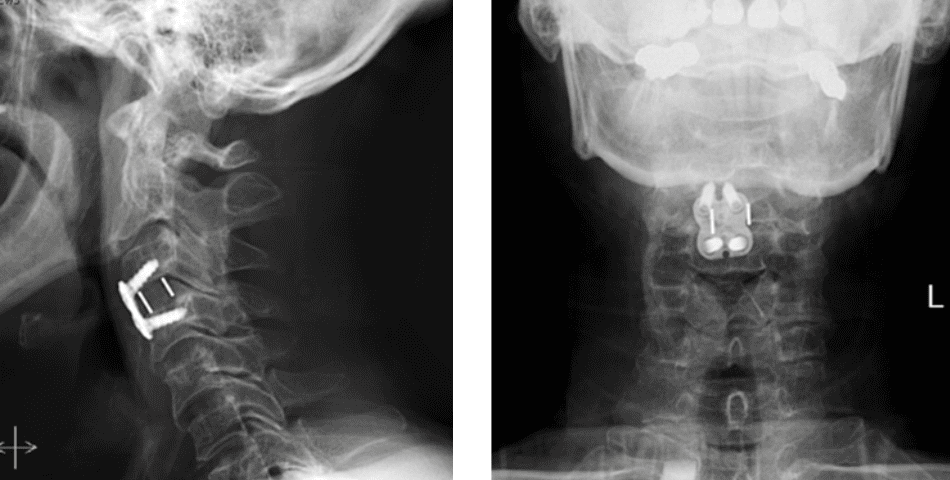

Dr. Imani performed an Anterior Cervical Discectomy and Fusion to remove the pressure of the herniated disc from compressing the spinal cord and stabilizing the spinal column with a fusion of the C3/C4 disc space.

Figure 2. Lateral and AP cervical spine x-rays s/p ACDF